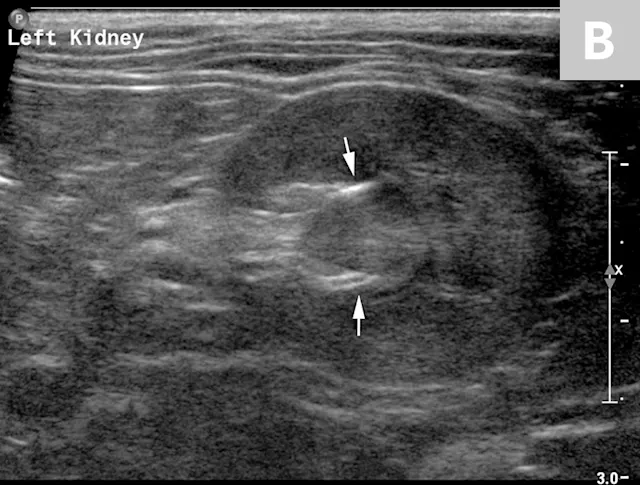

FIGURE 6A

1 / 2

Mild to moderate right hydronephrosis and proximal ureteral dilation in a Dalmatian.